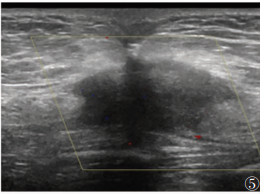

① 脐尿管平滑肌瘤1例,肿块位于脐尿管近膀胱顶部,超声显示脐下缘腹壁与膀胱顶部固定低回声肿块,边界清,形态规则;CDFI示病变内未见明显血流信号(图 3)。②脐尿管腺癌1例,超声表现为膀胱顶部非均质回声肿块,边界清晰;CDFI示肿块周边可见点状血流信号,RI增加(图 4)。③脐部转移瘤3例,超声均呈低回声结节、分叶、毛刺状,内可见斑点状高回声(图 5),内部回声与原发瘤性质相关;CDFI示2例结节可见少许血流信号,1例血流丰富。④脐部炎性肉芽肿1例,脐部不规则低回声肿块,边界清;CDFI示病变内少许血流信号(图 6)。

| 图 5 女,47岁,脐部转移瘤。脐部及深层肌层不规则低回声团块 |